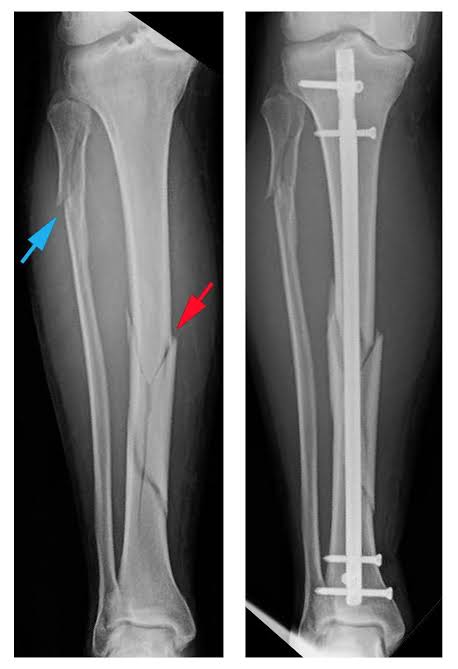

Pada kasus patah tulang,kadang dilakukan operasi utk memfiksasi tulang tujuannya agar posisinya bagus,sembuhnya bagus, bisa aktivitas lagi sprt sedia kala

Abis tulang yg patah dikembalikan ke tempatnya, kan harus dipegang dgn implant biar ga lepas lagi, biar terfiksasi bagus sampai tulangnya menyatu dan nantinya akan dilepas, implant nya klo dimasyarakat sering di sebutnya pen(plate and screw). Pen ini bisa dipasang diluar : Image

Selain pen yg dipasang di luar/permukaan tulang, pen bisa jg dipasang di dalam tulang(intramedullary nail/rod) ,antara yg di luar atau di dalam punya keunggulan masing2,sesuai kasus atau jenis patah tulangnya .. ImageImage

Atau bisa juga dipasang di dalam tulang (intramedullary nail/rod) .

Kenapa ada yg dipasang di luar ada yg di dalam?masing2 punya keuntungan sendiri2, tergantung jenis kasus patah tulangnya .. ImageImage